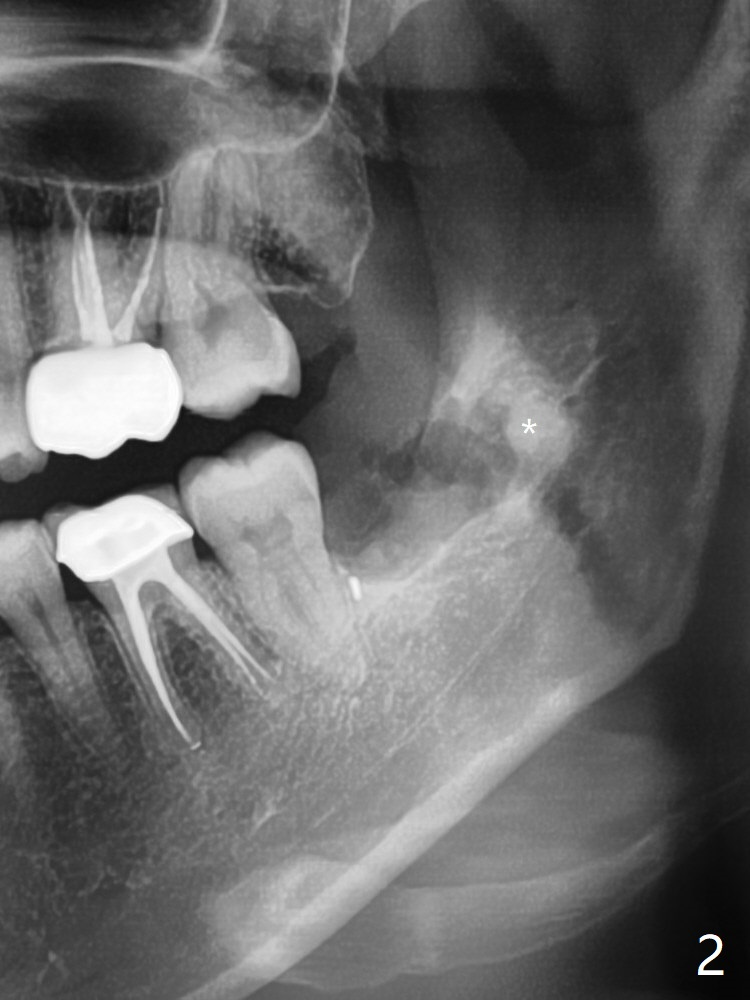

The fractured root tip (Fig.2 *) is so deep that the longest surgical length fissure bur can not reach in spite of multiple sectioning.  The nervous patient agrees not to remove the root tip because of pain associated with root tip loosening.  The fractured bur tip cannot be found clinically.  CBCT should have taken for bur location and the proximity of the root tip to the Inferior Alveolar Canal.  Bone fills the socket 1 year postop (Fig.4).  智齿充分挺松(牙根与牙槽骨分离,牙周膜断裂)后,才劈开牙齿:磨刀不误砍柴工。